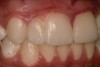

Following soft-tissue maturation, the desired shades with characterization were selected including the gingival shade for the pink porcelain, and fused teeth Nos. 7 to 8 and tooth No. 9 were prepared for veneers (Figure 11). Care was taken to dip into the preparation facially at the interface between the proposed central-lateral teeth, and shorten the distal-incisal to provide room for the laboratory to create the appearance of two separate teeth with a shorter lateral incisor. Retraction cord was placed for gingival displacement, the zirconia coping was inserted on the implant abutment, and an impression of the fused teeth Nos. 7 and 8 and tooth No. 9 was made, picking up the zirconia coping (Figure 12).

Fig 11. Fused teeth Nos. 7 and 8 and tooth

No. 9 were prepared for veneers.

Fig 12. Impression of the fused teeth Nos. 7 and 8 and tooth No. 9.